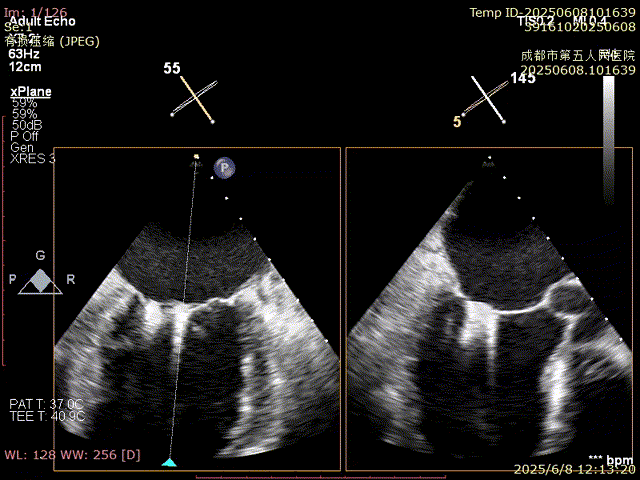

術(shù)前超聲

VFMR,反流2區(qū),新分型CCA型,MR重度(VC:3*14mm),A2:21mm,P2:10-11mm,AP:30mm,前后葉間3mm gap,MVA約5.1cm²